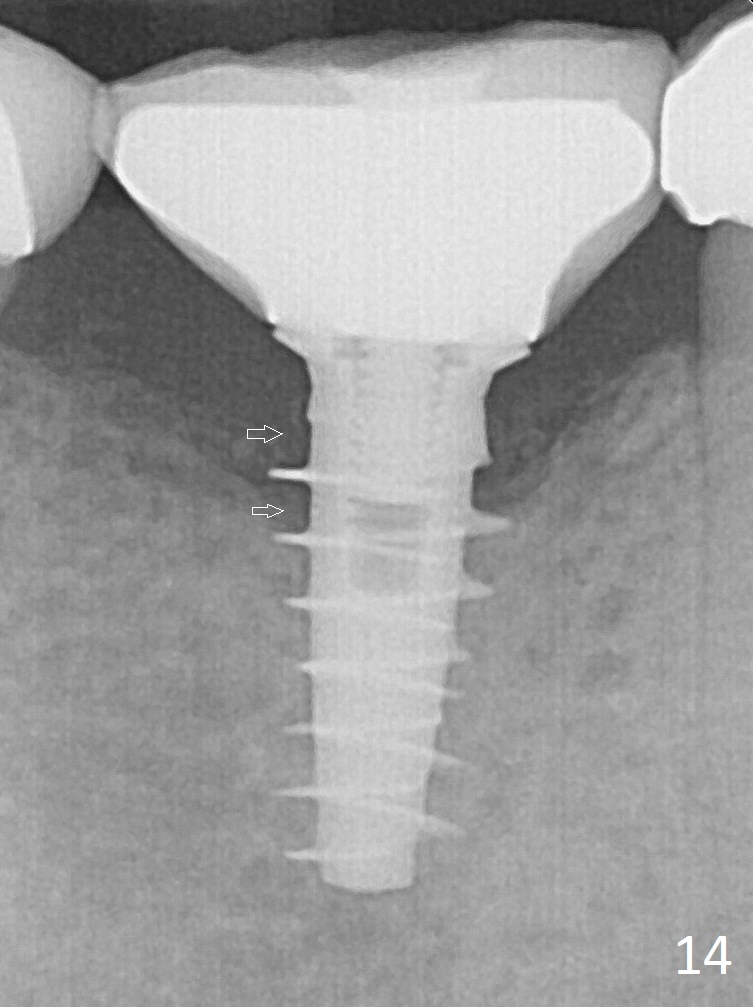

PA is taken immediately post tightening and cementation (Fig.14, 5 months postop). It appears that new bone has grown between the most coronal threads (arrows).